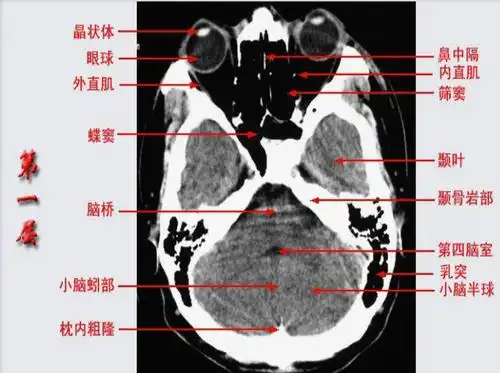

超精致颅底断层解剖(必点收藏)

10张图搞定正常头颅ct断层解剖

(图) 脑底横断层ct像-人体解剖学标本-医学

纯手工详细标注颅底解剖太赞了